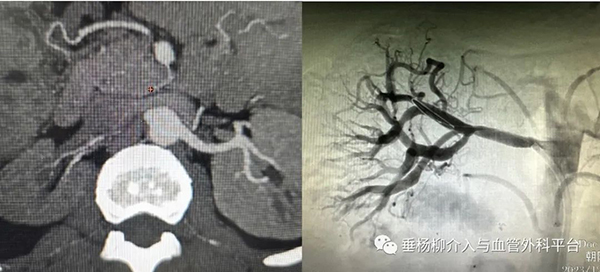

术前 右肾动脉未显示 术后 右肾动脉血流通畅

经过周密的手术计划,12月14日,赵女士的手术在医院第一手术区复合手术室正式开始。由于赵女士术前血压高达205/130mmHg,经药物降压准备后,肾动脉微创开通紧张而有序的进行。术中,血管外科团队始终保持专业和冷静,耐心寻找右肾动脉开口,多次尝试后终于使导丝通过闭塞的肾动脉段进入远端血管真腔,轻柔缓慢的扩张、精准定位后植入肾动脉支架,经过一个小时的精心操作,手术终于成功完成!

术后,赵女士的血压很快得到有效控制,那些反复出现的头晕、头痛、恶心等症状也得到了明显缓解。12月18日,赵女士顺利出院。医院血管外科团队用精湛的专业技术保住了患者的肾脏,用爱心和实际行动证明了医者仁心的真谛和勇往直前的精神,为赵女士带来了希望和信心。